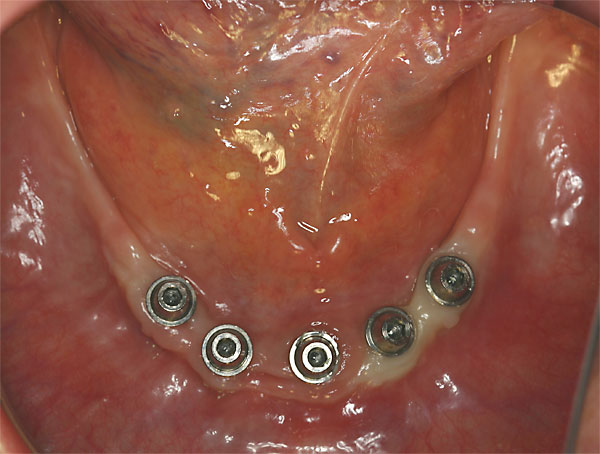

FOTO Abdruckpfosten im Mund zur Übertragung auf das Meistermodell |

FOTO festsitzende Brücken im Mund |